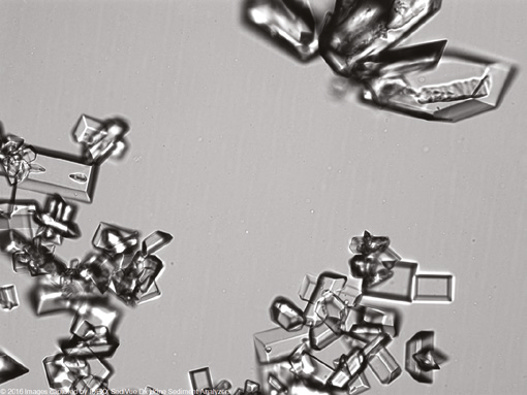

图2  (a)鸟粪石(未染色尿沉渣)。成簇的鸟粪石和两个X形的大晶体。(b)鸟粪石晶体。高倍图显示该晶体的边缘和三维性质。(c)鸟粪石晶体。两个晶体相互垂直生长。图片来自Dr. Michael Horton, Fairborn, OH